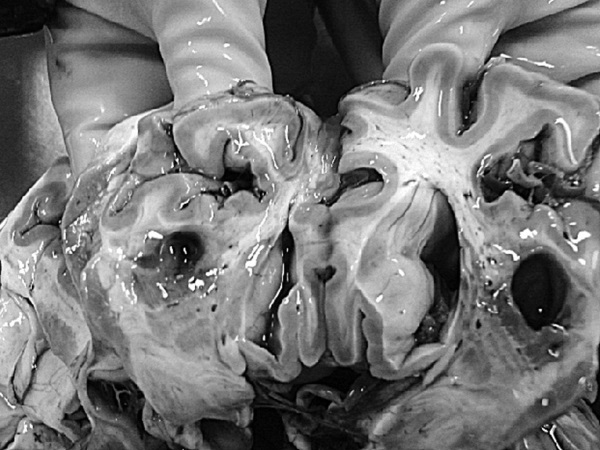

На секции был установлен следующий диагноз.

Основной:

1. Последствия инфаркта головного мозга. Внутренняя гидроцефалия. Атеросклероз артерий виллизиева круга.

2. ИБС. Постинфарктный кардиосклероз. Атеросклероз коронарных артерий.

Фоновый:

1. Артериальная гипертензия.

2. Гипертрофия левого желудочка сердца.

Осложнения:

1. Длительная иммобилизация.

2. Хроническая сердечная недостаточность.

3. Невроангиосклероз.

4. Пролежни.

5. Интоксикация.

6. Отек головного мозга.

Сопутствующий:

Доброкачественная гиперплазия предстательной железы

Последствия ОНМК: постинфарктные кисты головного мозга

Постинфарктный кардиосклероз

Атеросклероз сосудов головного мозга. Отек головного мозга

Атеросклероз коронарных артерий

Гипертрофия левого желудочка

Мускатная печень

Полнокровные легкие

Рис. 1. Результаты аутопсии больного 68 лет